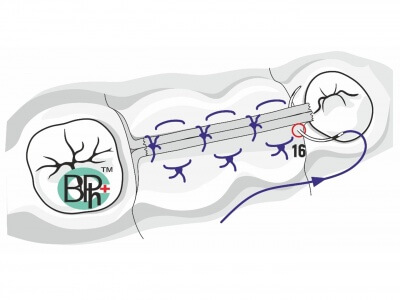

При этом, чем выше мы поднимаем слизистую пазухи тем больше кровоснабжения из соседних участков мы можем получить (рис 2).

При этом, чем выше мы поднимаем слизистую пазухи тем больше кровоснабжения из соседних участков мы можем получить (рис 2).  Сосудистая сеть наружной стенки носа многослойная и обильная. Следовательно, получить кровоснабжение из данного источника очень легко. Для этого необходимо как можно выше отсепарировать слизистую пазухи с носовой стенки. Благодаря этому мы получаем несколько плюсов. Во первых, напряжение слизистой уменьшается она становиться складчатой. Это предупреждает возникновение разрывов и трещин во время аугментации. Во вторых, мы получаем доступ к месту с обильным кровоснабжением которое крайне необходимо для последующего костеобразования и ремоделирования костной ткани.

Сосудистая сеть наружной стенки носа многослойная и обильная. Следовательно, получить кровоснабжение из данного источника очень легко. Для этого необходимо как можно выше отсепарировать слизистую пазухи с носовой стенки. Благодаря этому мы получаем несколько плюсов. Во первых, напряжение слизистой уменьшается она становиться складчатой. Это предупреждает возникновение разрывов и трещин во время аугментации. Во вторых, мы получаем доступ к месту с обильным кровоснабжением которое крайне необходимо для последующего костеобразования и ремоделирования костной ткани.